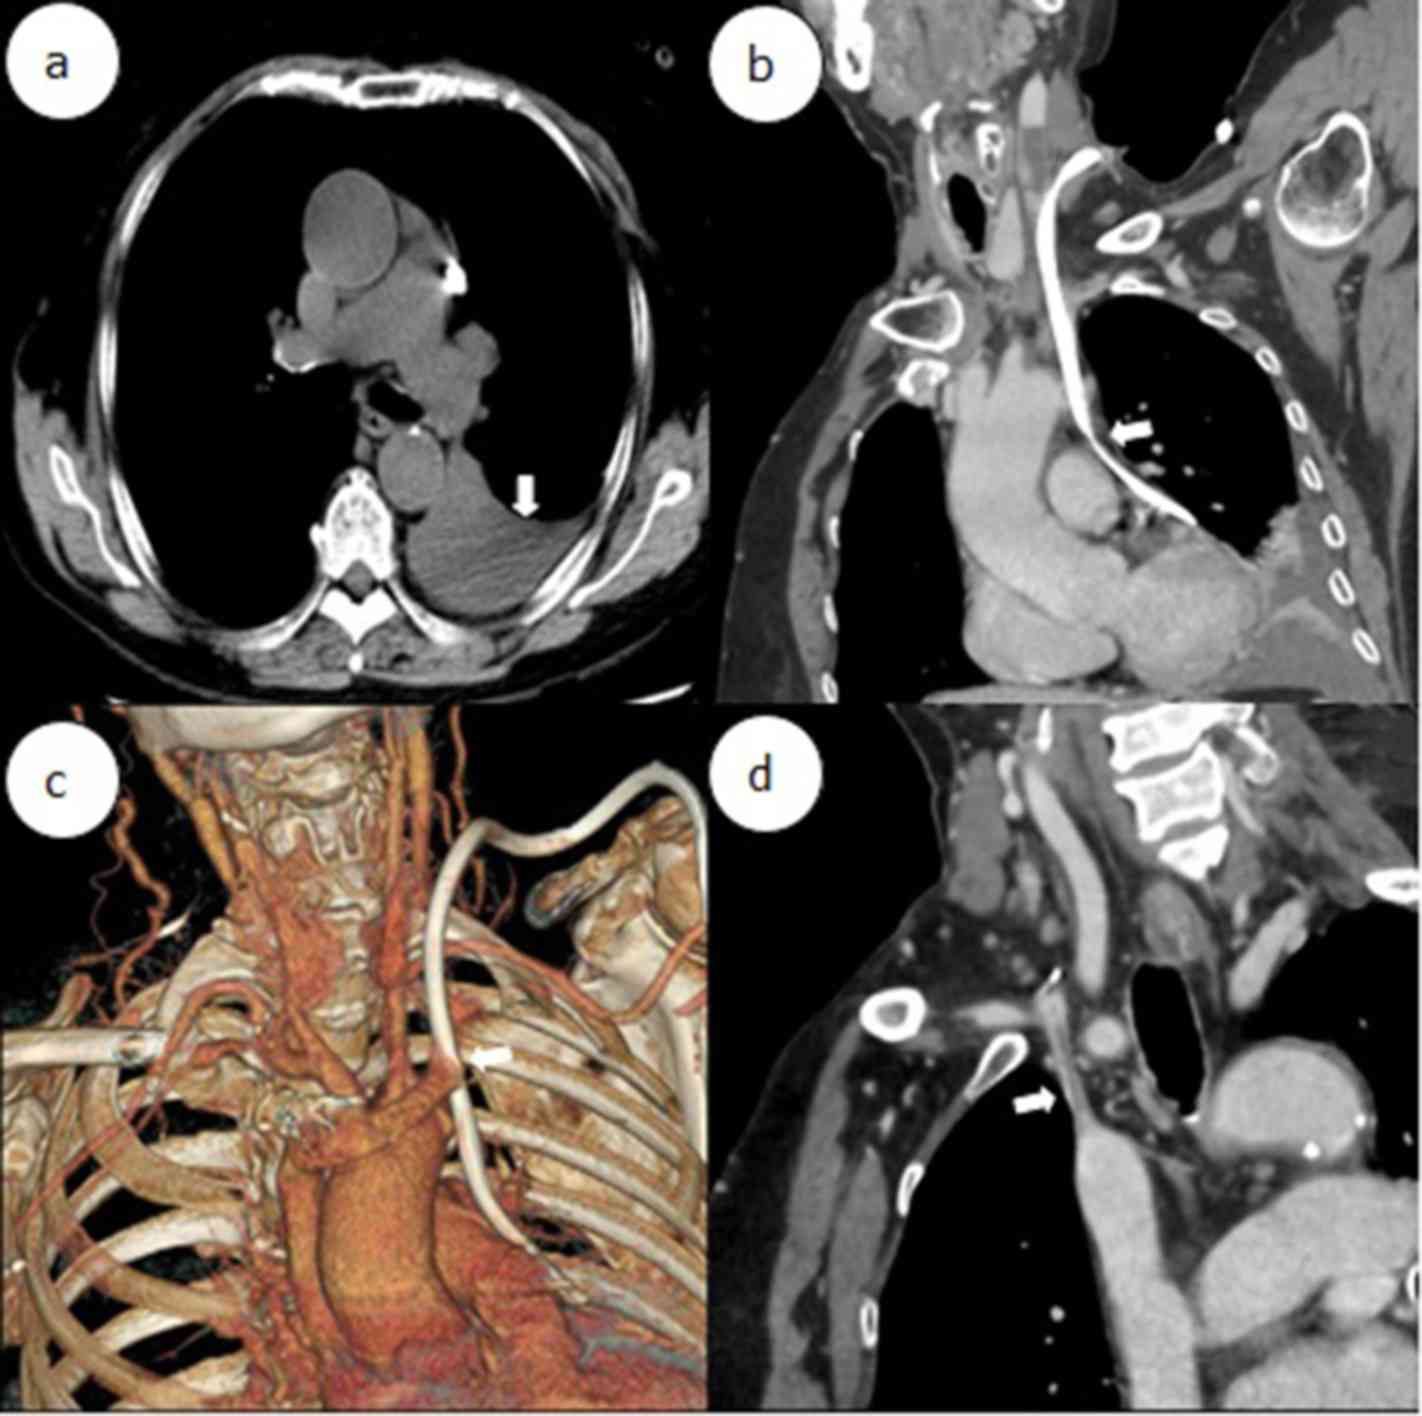

The present study reported a case of left BCV perforation that was diagnosed at the First Affiliated Hospital of the University of Science and Technology of China (USTC; Hefei, China). The present study was approved by the Ethics Committee of The First Affiliated Hospital of the USTC and informed consent was also obtained from the patient. A 64-year-old female with a 15-year history of hypertension underwent left forearm arteriovenous fistula (AVF) surgery to treat stage-V chronic kidney disease (CKD) five years previously. One month prior to presentation at our department on June 8, 2017, the patient had a fistula obstruction and a local hospital placed a temporary catheter in the patient's right femoral vein for hemodialysis. However, the inserted catheter caused occlusion of the right BCV. Review of the patient's medical history revealed that she received a long-term hemodialysis catheter (hemosplit 14.5F/23 cm; BARD) via the left internal jugular vein (LIJV) two days prior to occurrence of HS. LIJV punctures using the Seldinger technique were performed under local anesthesia, followed by smooth introduction and positioning of the guidewires in the left IJV to a level just below the diaphragm. After dilator and guidewire removal, the catheters were introduced, followed by removal of the peel-away sheaths. When placing the catheters, the surgeon felt a marked resistance. Furthermore, the patient reported mild pain and discomfort in the left chest during the catheterization process. After the completion of catheterization, hard venous blood was aspirated. The surgeon considered the possibility of acute thrombosis. A total of 200,000 units of urokinase were injected into the catheter, revealing obstructed flow after 20 min. Subsequently, the patient developed symptoms of palpitations, chest stuffiness and cold sweats. Thoracic anteroposterior radiography at the emergency department indicated that the body segment of the dialysis catheter was located on the left side of the mediastinum (Fig. 1). Therefore, the patient was rapidly transferred to our hospital. Upon admission, general and systemic examinations were unremarkable except for pectoralgia on the left side and chest tightness accompanied by asthma or breathing difficulties/obstruction, an elevated heart rate (115 beats/min) and hypotension (blood pressure, 82/45 mmHg). Laboratory investigations revealed a red blood cell count of 1.72×1012/l (normal range: 3.5~5.5×1012/l) and a hemoglobin level of 59 g/l (normal range: 110–150 g/l). A contrast-enhanced chest computed tomography scan revealed that the left BCV was perforated through the mediastinum and entered the left thoracic cavity, with the appearance of pleural effusion (Fig. 2a-d). A pleural puncture was performed to extract nonclotting blood. According to the above symptoms, the patient was diagnosed with central venous perforation and HS. The patient immediately received anti-shock treatment by fluid infusion and blood transfusion. The patient was given 6 U total transfused red blood cells and 800 ml fresh frozen plasma. Subsequently, the patient's blood pressure rose to 90–100/50–60 mmHg and the heart rate was reduced to 100–110 beats/min. However, there were obvious symptoms of pectoralgia, which was aggravated when breathing and coughing. Since the patient had evidence of a bleeding disorder with unstable vital signs, it was decided to perform intracavitary treatment to repair the damaged blood vessels. A total of 10 µl non-ionic contrast medium (Iodixanol; 27 g/100 ml; Amersham Health) was injected into the dialysis catheter, and X-ray fluoroscopy indicated that the contrast agent entered the left thoracic cavity through the front of the dialysis catheter and quickly dispersed (Fig. 3).

Figure 2.

(a) the arrows indicated left pleural effusion. (b and c) the arrows indicated catheter passing through the left brachiocephalic vein into the left thoracic cavity. (d) The arrows indicated right brachiocephalic vein occlusion.